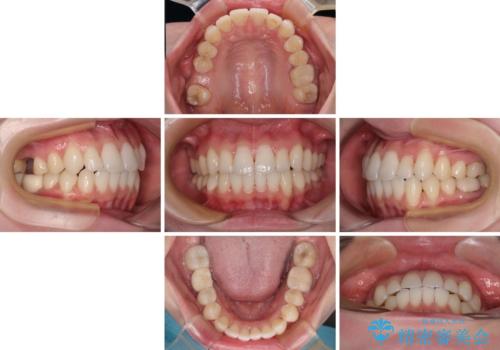

ワーキングホリデー前にきれいな歯列に

- 2、3年後にワーキングホリデーで海外に行くため、その前に歯列やむし歯をきれいにしたいとのことで来院された患者様です。

抜歯の必要な右上の奥歯は事前に抜歯をし、インビザラインにて上下歯列を整えることとしました。

矯正治療後半に奥歯の補綴治療が必要な歯にはオールセラミッククラウンを装着し、インビザラインで最終的に仕上げることとしました。

海外に行く前に口腔内環境を整えることができ、患者様には大変満足していただきました。